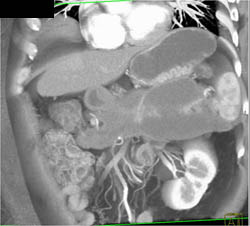

Pancreatic Cancer With Implants on the Omentum